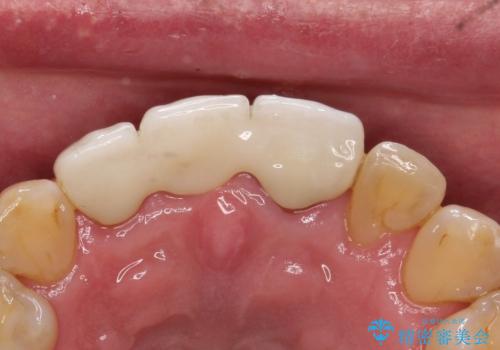

【オールセラミックスタンダード】前歯のブリッジ

- 矯正治療終了後の患者様です。

前歯が欠損しており、ブリッジでの修復を希望されましたので、オールセラミッククラウン(スタンダード)で治療を行いました。

より審美的に色調や形態をこだわりたい場合はオールセラミッククラウンのスペシャルやエクセレントにグレードを上げていただくことで可能です。